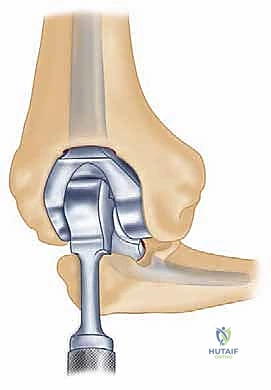

تعتبر جراحة استبدال المرفق من الجراحات التي تتطلب دقة هندسية عالية. يستخدم الدكتور محمد هطيف أحدث التصاميم للمفاصل الصناعية (عادةً ما تكون من التيتانيوم ومادة البولي إيثيلين عالية الكثافة).

5. زراعة المفصل الصناعي (Implantation)

يتكون المفصل الصناعي من قطعتين معدنيتين رئيسيتين (جزء عضدي وجزء زندي) وبينهما مفصلة بلاستيكية (Hinge) توفر الحركة السلسة.

يتم تثبيت هذه الأجزاء المعدنية داخل القنوات العظمية باستخدام الأسمنت العظمي الطبي (Bone Cement)، وهو مادة خاصة تضمن تثبيتاً فورياً وقوياً، وهو أمر بالغ الأهمية لمرضى الروماتويد الذين يعانون من هشاشة العظام.

يتم تجميع المفصل الصناعي وربط الجزء العضدي بالجزء الزندي بواسطة مسمار مفصلي (Pin)، مما يعيد للمرفق استقراره المفقود.